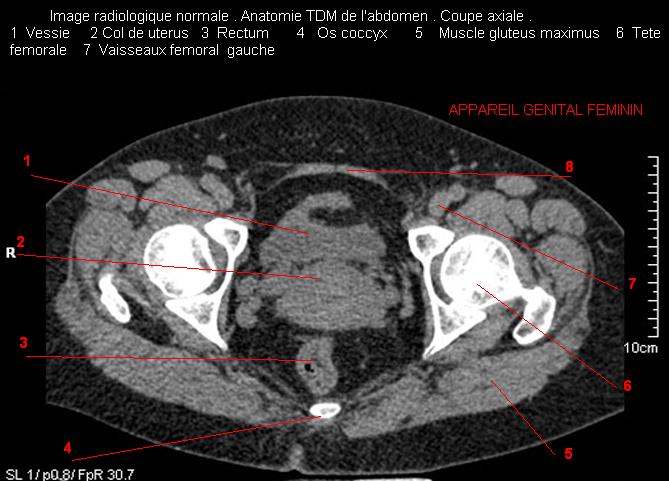

Images radiologique TDM normale de l'abdomen et tube digestif  en coupe axiale ( CT scanner )  :

Coupe axiale     Coupe frontale      Coupe  sagitale